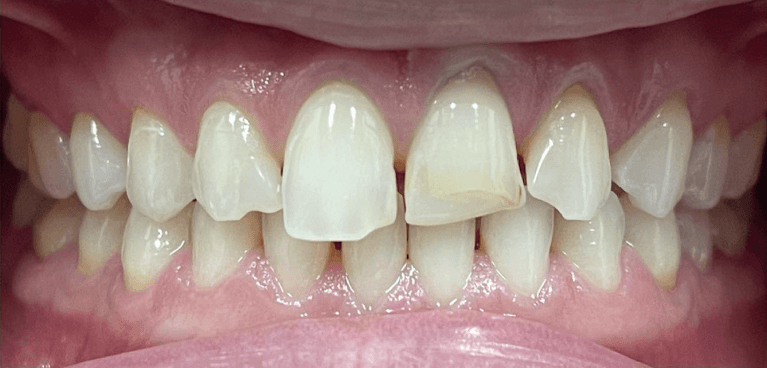

Before and after with Invisalign orthodontic treatment. Pictures taken with different phones at different setting. Used total of 27 aligners/trays. Treatment time 13.5 months